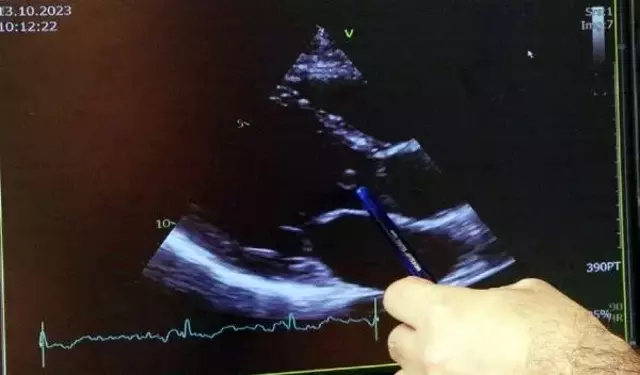

İstanbul'a gelen Çiftçi'nin enfeksiyon nedeniyle harap olan kalp kapağı, Marmara Üniversitesi Pendik Eğitim ve Araştırma Hastanesi Kalp Damar Cerrahisi, Hematoloji ve Yoğun Bakım ekiplerinin mucizevi çabası sonucu başarıyla değiştirildi. Toplamda 22 ünite kan verilen genç mühendis, yaklaşık 5 saat ameliyatta kaldı. Kalp ameliyatı sonrası sızıntı riski nedeniyle yoğun bakımda 24 saat kalbi açık bir şekilde izlendi. Doktorları taşıdığı risk nedeniyle ilk ameliyat sonrası gece yarısına kadar hastaneden ayrılmadı. Kanamaya bağlı sızıntı giderilerek göğüs duvarı ertesi gün yapılan ikinci ameliyatla kapatılabildi.

Açık kalp ameliyatı sonrası yoğun kanama problemi yaşadıklarını ve hastayı göğüs duvarı açık bir şekilde yoğun bakıma aldıklarını anlatan Prof. Dr. Ak, "Göğsü kapatamama durumu ortaya çıktıktan sonra, kanamayı kontrol altına alabilir miyiz diye çok büyük bir endişe yaşadık. Hematoloji hocamız da hastanın başındaydı. O gece, gece yarısına kadar hastanede kaldık. Yaklaşık 24 saat bu şekilde takip ettik ve bu şekilde bile sızıntıların devam etmesi nedeniyle tekrar ameliyata aldık. Göğsü ikinci ameliyatta kapattık. Bu esnada da sürekli kan ve kan ürünü transfüzyonu ile faktör replasmanı yaptık. Toplamda 20-22 ünite kan kullandık. Normalde belki 1 ünite, belki hiç kullanmayız" ifadelerini kullandı.